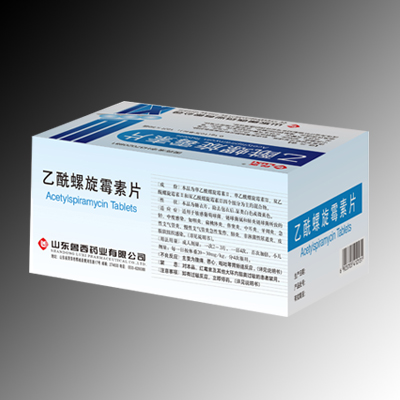

乙酰螺旋黴素片

乙酰螺旋黴素片 -